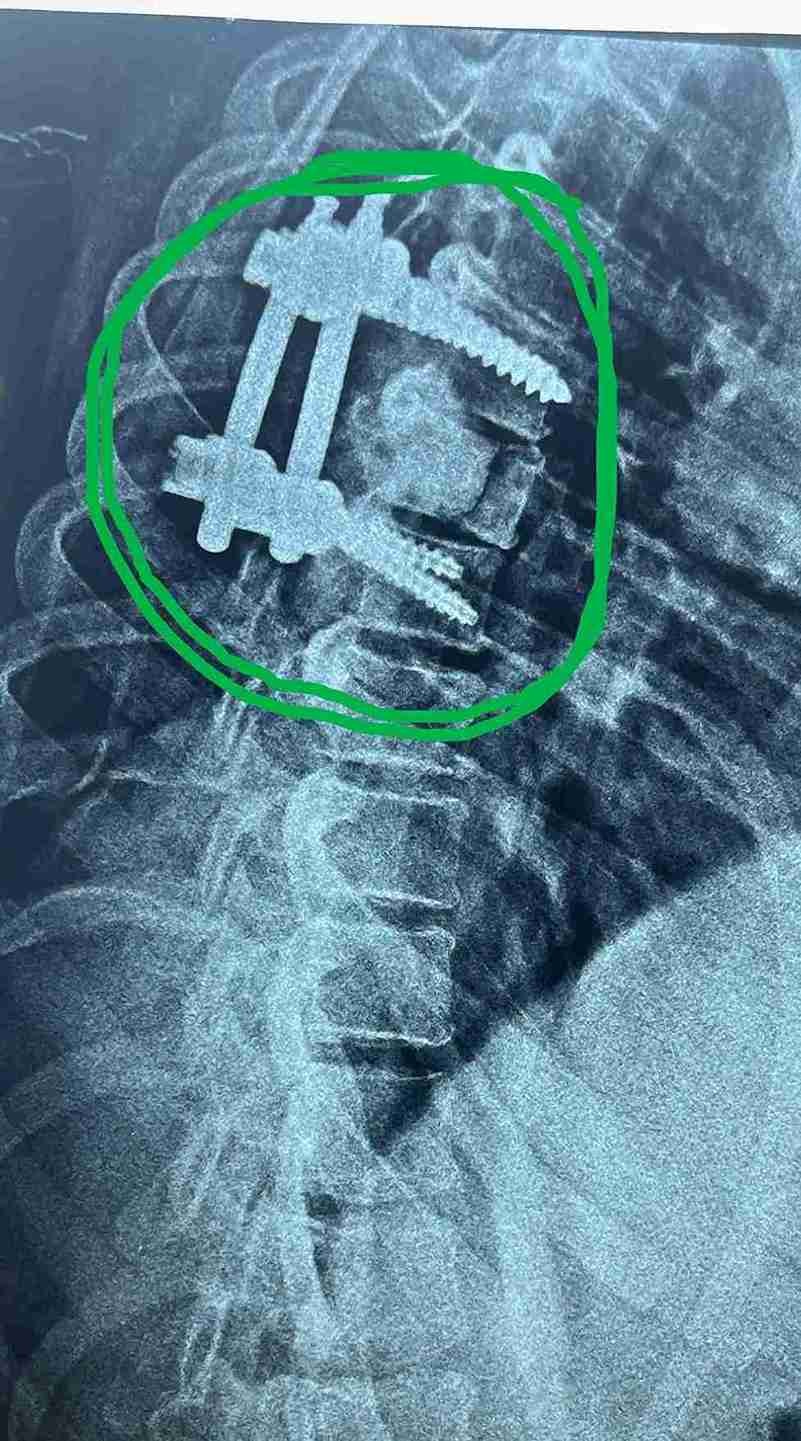

تم عمل جراحة ناجحة لاستئصال الورم بجسم الفقرة والتعويض بنظام تثبيت امامي عبارة عن اسمنت عظمي وخلفي عبارة عن مسامير وقضبان  تيتانيوم .

وذلك موضح بصور الاشعات قبل وبعد الجراحة . وقد تحسنت المريضة واستعادت كامل الوظايف العصبيىة واصبحت تمارس حياتها بصورة طبيعية.